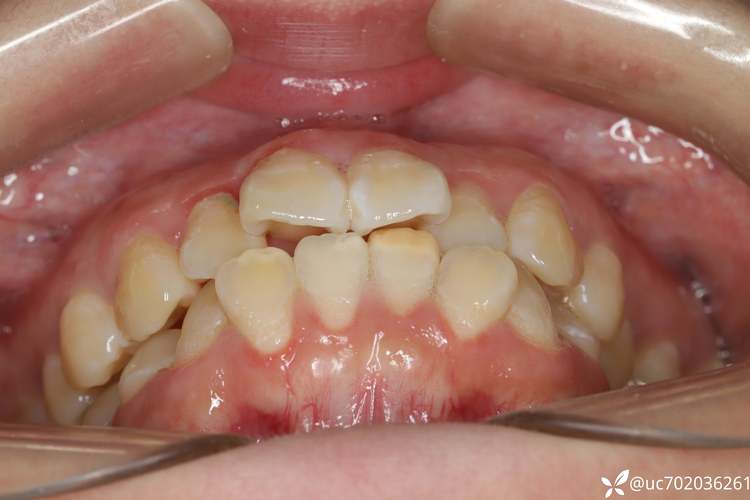

牙齿拥挤是口腔正畸领域最常见的错颌畸形类型,表现为牙齿在牙弓内排列紊乱、相互重叠或扭转,不仅影响面部美观,还可能引发清洁困难、龋齿、牙周病、咬合功能异常等问题,据统计,我国约70%的错颌畸形患者存在不同程度的牙齿拥挤,而矫正过程中是否需要拔牙,成为许多患者和家属最纠结的核心问题,拔牙并非矫正的“必选项”,而是医生在全面评估口腔状况、面部特征及生长发育情况后,为实现长期稳定治疗效果而采取的“精准手段”。

牙齿拥挤的本质是“牙量-骨量不匹配”——即牙齿总宽度超过了牙弓所能容纳的空间,就像小房间试图摆放太多家具,必然导致拥挤杂乱,这种不匹配的成因复杂:

当拥挤程度较轻时,可通过扩大牙弓、邻面去釉(磨除少量牙釉质)等方式“挤”出空间;但中重度拥挤(如上下牙弓总拥挤度超过10mm)、存在牙齿完全重叠或严重扭转(>45°)时,单纯靠移动现有牙齿难以实现稳定效果,此时拔牙“减数”成为更优解。